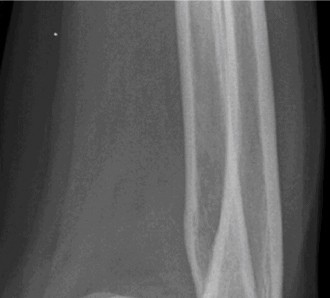

A 54-year-old male presented to the ED with left elbow pain after sustaining an injury in a low speed motor v…